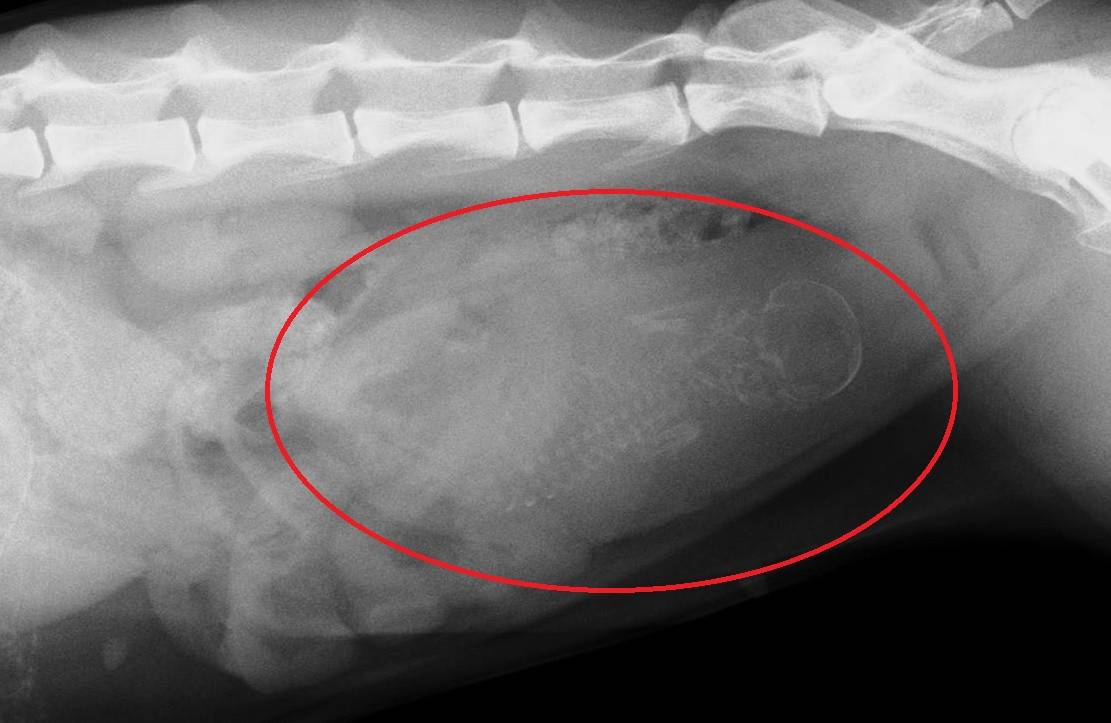

これが人工授精実施51日後に撮影したレントゲン写真です。

分かるでしょうか?

無事に胎児が1頭確認できました。